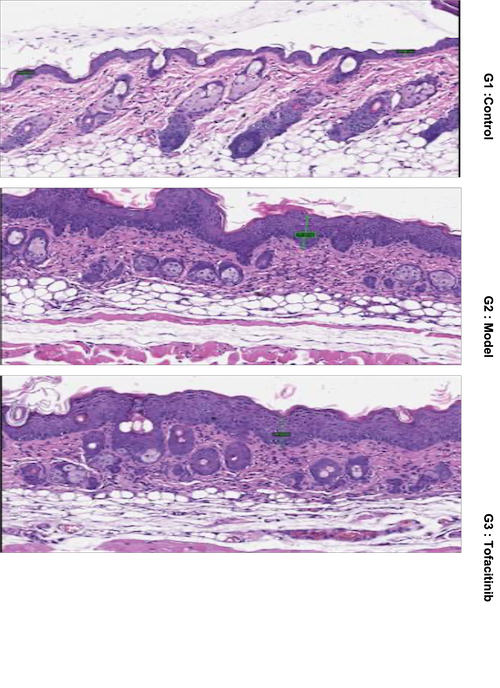

Animal: BALB/c mice, female, 7.5 weeks

Modeling: IMQ painted on shaved back skin daily

Reference Drug: Tofacitinib, p.o., BID

Readouts: Body weight, PASI score, skin thickness, pathology